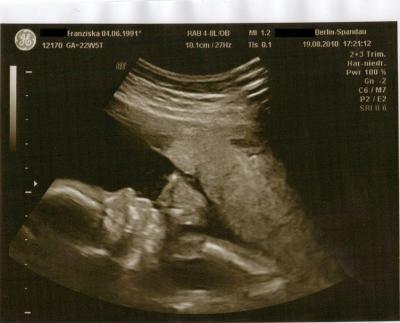

Sooo. Nun hatte auch ich gestern meine Feindiagnostik :D Es war soo schön das alles zu sehen Und es ist alles bestens! Es ist alles dort wo es sein muss, es ist alles so groß wie es sein muss, und es tut alles das was es tun muss ;D Baby wiegt jetzt so 514 gr. Oh man ich schlepp nen halbes Kilo Baby mit mir rum. Schon irgendwie komisch Und es hat sich diesmal auch nochmal bestätigt das es ein Mädchen wird, das wär ja was gewesen wenn da aufeinmal ein Pipimann gewesen wäre lach. Hat sich anfangs erstmal hinter ihrer Hand versteckt, zwischendurch hat sie dann doch ihr Gesicht gezeigt und mein FA hat ein schönes Bild davon machen können Er hat mich auch nach Hebamme und Krankenhaus gefragt, ob ich schon welche in aussicht hab und fragte ob ich dort entbinde wo meine Schwester entbunden hat (was der sich so alles merkt, wo meine Schwester vor 4 Jahren entbunden hat lach) und hat mir dann noch ein Heft mitgegeben mit allen Kliniken in Berlin und was die anbieten etc. :) Ich glaube der hatte aber bisschn schlechte laune, war scheinbar viel los an dem Tag. (waren insgesamt fast 2 Stunden dort wovon ca. 1 Stunde Wartezeit war) Aber er hat sich bemüht sich nichts anmerken zu lassen ;D Ist ja auch schon ein alter Mann, der darf ruhig mal erschöpft sein am Abend Und mein Verlobter ist ganz begeistert! Heute früh als er los ist zur Arbeit hatte er total gute Laune, auf meine Frage hin wieso er so gut gelaunt ist meinte er: "Ich bin einfach glücklich das es unserem Baby gut geht!" Hach, wie süß! Und ab dem 14.10. muss ich schon alle 2 Wochen hin. Wie die Zeit vergeht Und nun zu meiner Frage: Ich bin der Meinung hier gelesen zu haben das man aus den Daten die Länge des Babys ausrechnen kann? Kann mir bitte jemand sagen wie??? Achja. Aktuelles Gewicht: 60,4 kg Hab mich schon gefürchtet vor der Zahl auf der Waage Aber es hat ja wenigstens einen guten Grund :) Mein aktueller Spitzname bei meinem Verlobten: Kugelbauch Und Babys Spitzname: mutierter Erdnussflip. Und morgen in einer Woche bin ich schon im 7. Monat Wünsche euch einen schönen Start ins Wochenende, hoffen wir das es gutes Wetter gibt! GLG, Franzi (die überglücklich ist ) P.S.: Profil-US von der Kleinen :)